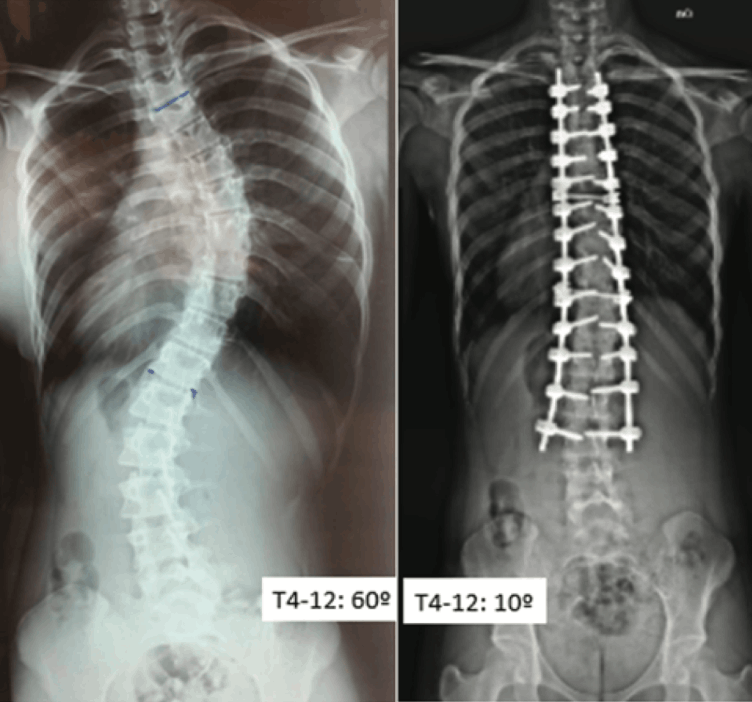

Retrospective Analysis of 52 Cases of Scoliosis Surgery in the Central-West Region of Brazil.

Por Dr. Chrystiano Fonseca Cardoso.

This retrospective study analyzed 52 patients who underwent scoliosis surgery between 2014 and 2023 in private hospitals in the Central-West region of Brazil. The objective was to evaluate the degree of curvature correction, using the Cobb method, and postoperative complications. The sample was predominantly female (86.6%), with a mean age of 16 years. The majority of patients (92.3%) were diagnosed with idiopathic scoliosis (IS), with 57.7% presenting thoracic curves and 34.6% presenting lumbar curves, according to the Lenke classification.

The average preoperative Cobb angle was 55°, with a postoperative average correction of 74%, reflecting the effectiveness of spinal arthrodesis techniques with pedicle screws.